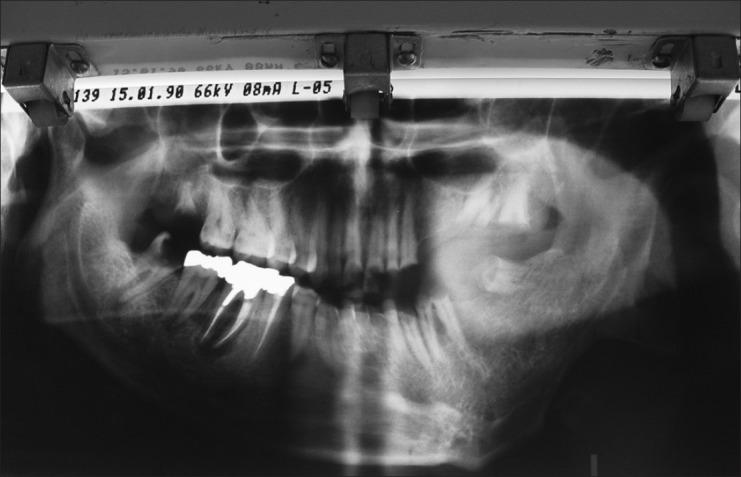

The term neurofibromatosis (NF) is used for a group of genetic disorders that primarily affect the cell growth of neural tissues. Neurofibromatosis type 1 (NF1), also known as von Recklinghausen's disease, is the most common type of NF, and accounts for about 90% of all cases. It is one of the most frequent human genetic diseases, with a prevalence of one case in 3,000 births. The expressivity of NF1 is extremely variable, with manifestations ranging from mild lesions to several complications and functional impairment. Oral manifestations can be found in almost 72% of the NF1 patients. The aim of this article is to report the NF1 in a family with different manifestations and to review the literature.

神经纤维瘤病(NF)一词用于指代一组主要影响神经组织细胞生长的遗传性疾病。1型神经纤维瘤病(NF1),也称为冯·雷克林豪森病,是最常见的NF类型,约占所有病例的90%。它是最常见的人类遗传病之一,发病率为每3000例出生中有1例。NF1的表现极为多样,从轻微病变到多种并发症和功能障碍都有。几乎72%的NF1患者会出现口腔表现。本文旨在报告一个具有不同表现的NF1家系并对文献进行综述。